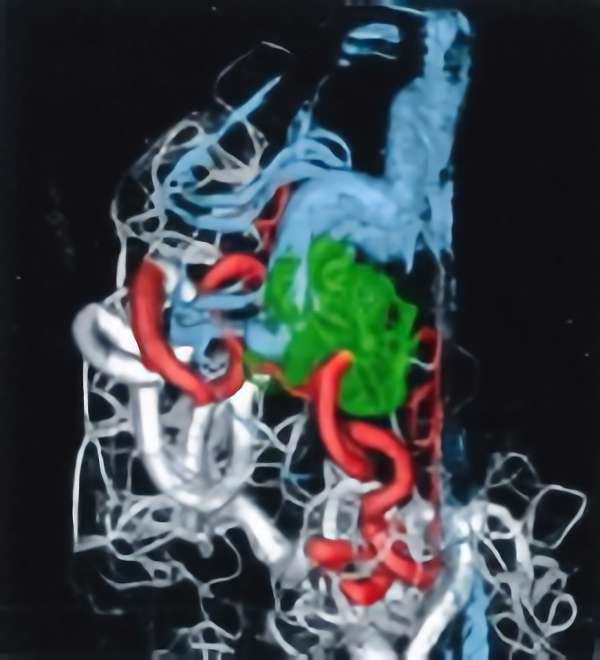

脳血管撮影

手術前

手術後

手術中

手術写真